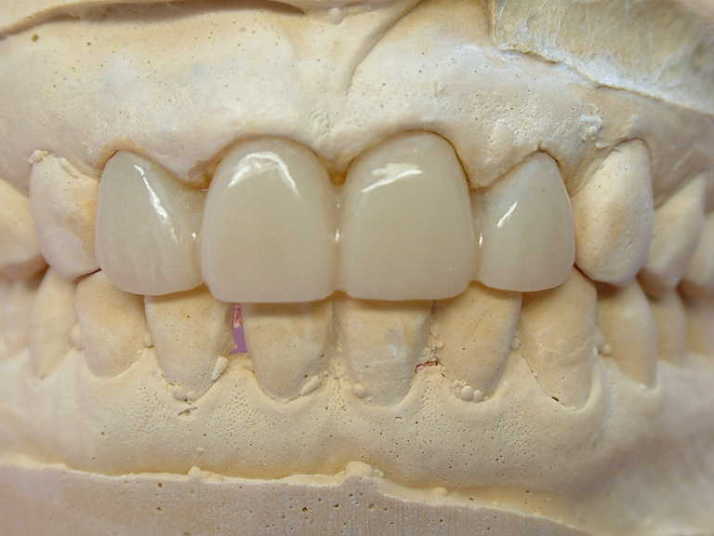

☆2.2の歯の幅を広げ、1.1の幅を狭くし

全体のバランスを取り作りたいと思います

☆1〜1の間の歯間空隙部分が不自然にならない

よう歯肉模型にて確認しながら製作します |